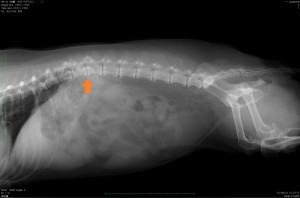

左の画像はX線写真で、左の画像はMRI検査の写真です。橙矢印が椎間板物質が飛び出していた部分ですが、X写真では脊髄の様子は分りませんが、MRI検査では脊髄が圧迫されている様子がよく分かります。